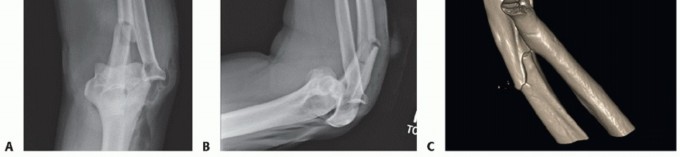

Serial x-rays are obtained to detect any loss of reduction at immediate postoperative, 2 weeks, 6 weeks, and 3 months, until healing is achieved (FIG 12).

- FIG 12 • Postoperative x-rays showing anatomic reduction of the radial head fracture. The Biotrak screws are radiolucent. Note that anchor holes are seen at the crista supinatoris where the lateral ulnar collateral ligament (LUCL) and annular ligament complex are repaired.